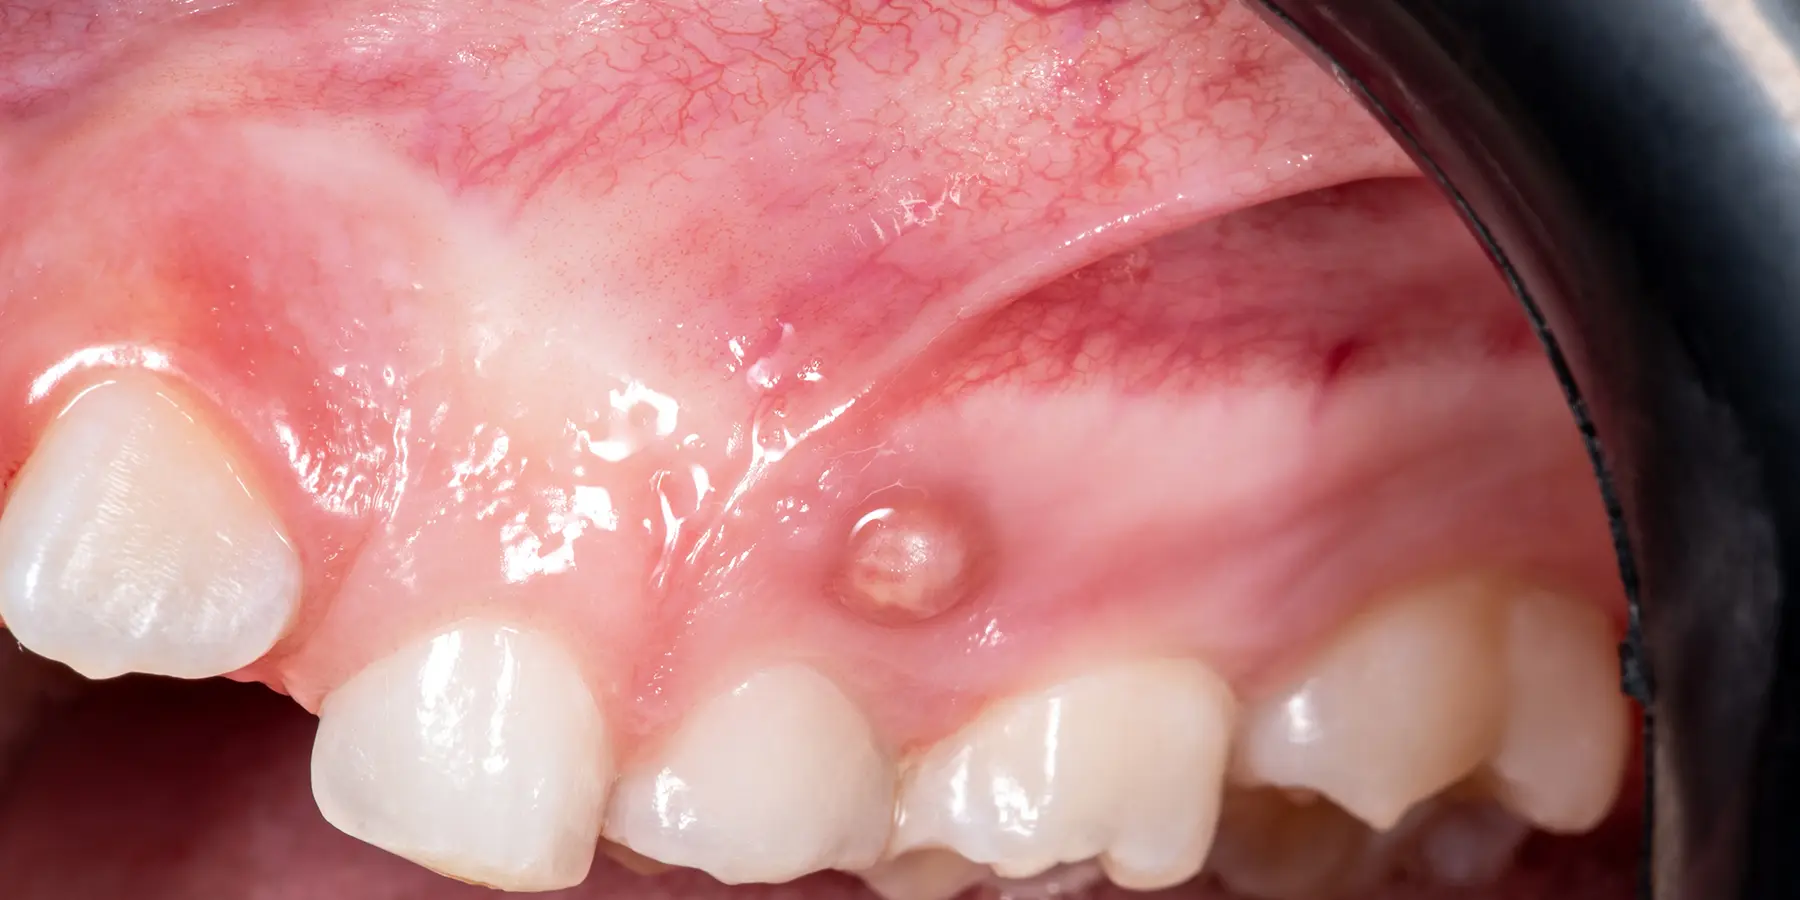

ممکن است متوجه توده یا برآمدگی در ناحیه آبسه شوید که با درد و فشار همراه است. همچنین موارد زیر از علائم این عارضه می باشند:

اگر این باکتری های مضر راهی به درون بافت لثه پیدا کنند، ممکن است در آنجا فضایی تشکیل دهند و زیاد شوند و در نهایت باعث عفونت شوند. تورم ناشی از ایجاد عفونت نشان دهنده ارسال گلبول های سفید بدن برای مبارزه با عفونت است. در نتیجه، منجر به ایجاد بافت متورم و دردناک پر از چرک به نام آبسه می شود.